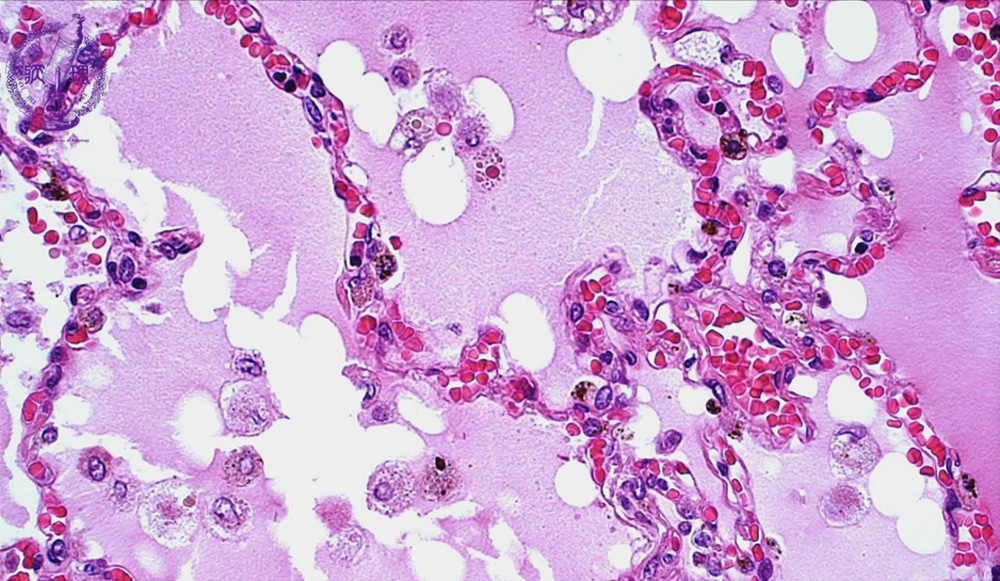

- 5.Lung, Pleura

- ★(1)Pulmonary edema

Microscopic view (HE stain, high power view): In this especially congested area, interalveolar septa show capillaries packed with red blood cells. There are many macrophages (arrow), which phagocytize the leaking plasma transudate and red blood cells.